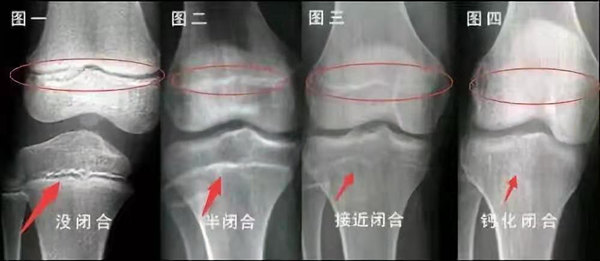

我們都知道,人體的高矮是由骨骼的生長發(fā)育決定的,特別是下肢長骨。長骨呈長管狀,在長骨的兩端有一種專管骨骼生長的骺軟骨,它與干骺端之間有一盤狀軟骨結(jié)構(gòu)稱為骺板(線),在幼兒的X光片上表現(xiàn)為一條較寬的透光帶。 (見下圖)

未成年時隨著年齡的增加骺軟骨端不斷骨化,骨骼就不斷增長。當(dāng)骨骺線完全閉合時骨骼就停止生長,個子也就不再增長了。一般骨骺端完全閉合的年齡是18~20歲左右。

一般來說,女孩的骨齡超過14歲,男孩的骨齡超過16歲,這時其骨骺線已接近閉合,基本沒有長高的機(jī)會了。

因此,越早了解骨骺線閉合情況,越早干預(yù),孩子長高的可能性越大。